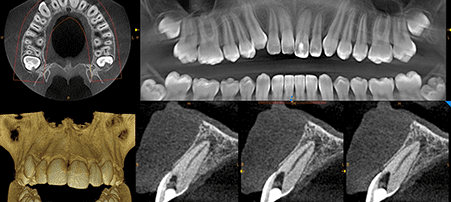

CBCT 3D Scanner

A state of the art scanning machine used to produce incredibly accurate and detailed 3D images. From single teeth to both upper and lower jaws in a single scan with a reduced radiation dose and high speed.

Extremely beneficial in detecting and diagnosing oral health problems and as an aid to planning of treatment. CBCT 3D Scanners are becoming extremely important as dentistry moves further into the digital generation.

- Oral Surgery

- Complex Endodontic cases